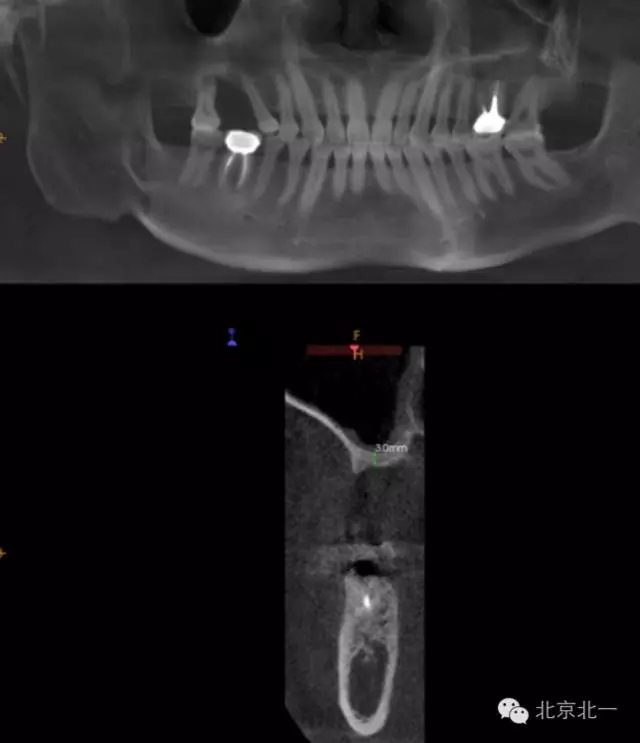

CBCT顯示,骨寬度可,骨高度不足,月3mm。頜間距離增大。

圖三:骨高度3mm.

圖十八:手術(shù)前CBCT

圖十九:手術(shù)后當(dāng)天CBCT